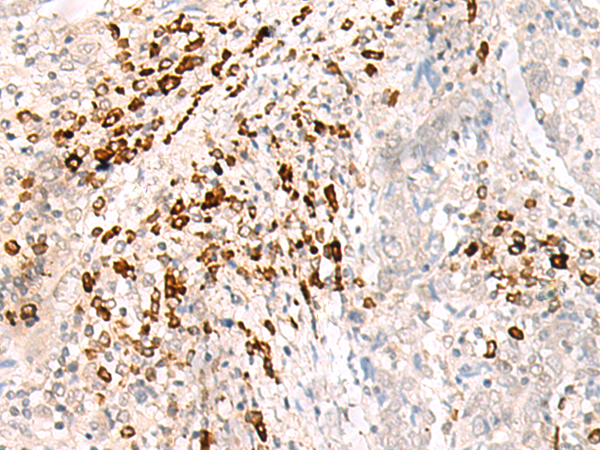

分类: 科研抗体货号: P06451别名: IL17; CTLA8; IL-17; CTLA-8; IL-17A应用: IHC反应种属: Human